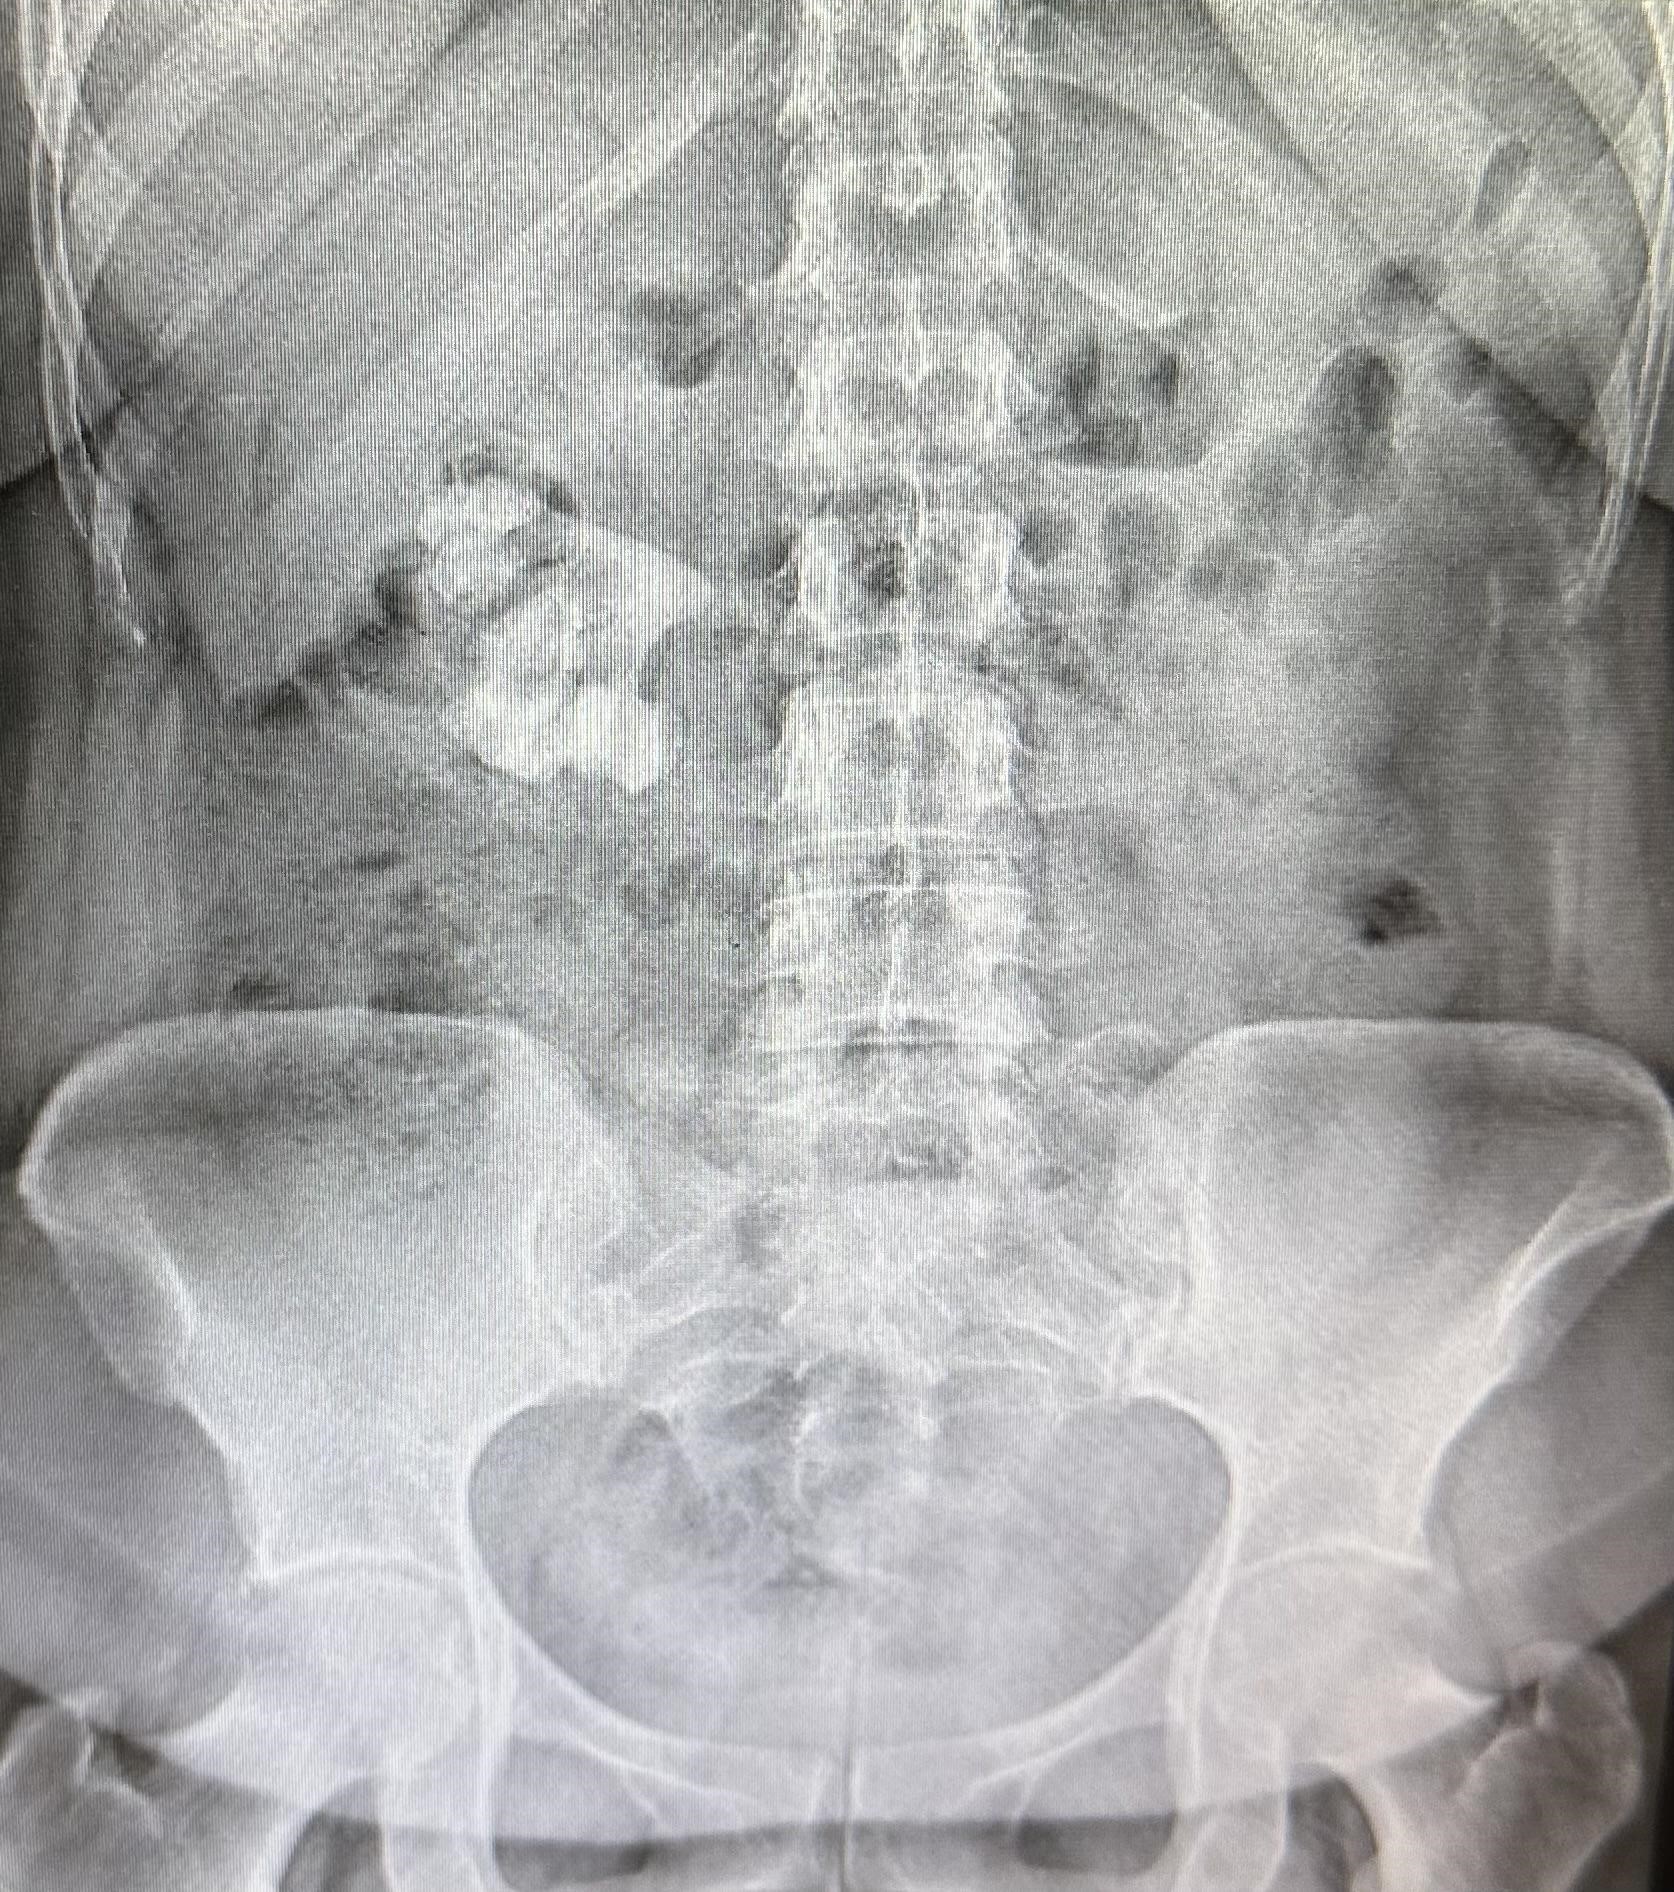

RADIOGRAFÍA

En el flanco derecho, se observa imagen radiopaca de gran tamaño con morfología característica en “cuerno de ciervo”, ocupando la silueta renal derecha (figura 1), hallazgo compatible con litiasis coraliforme completa derecha.

Imagen 1: Radiografía simple de abdomen y pelvis en proyección anteroposterior: litiasis coraliforme completa. Fuente: departamento de radiología médica del Hospital Regional Dr. Rafael Hernández.